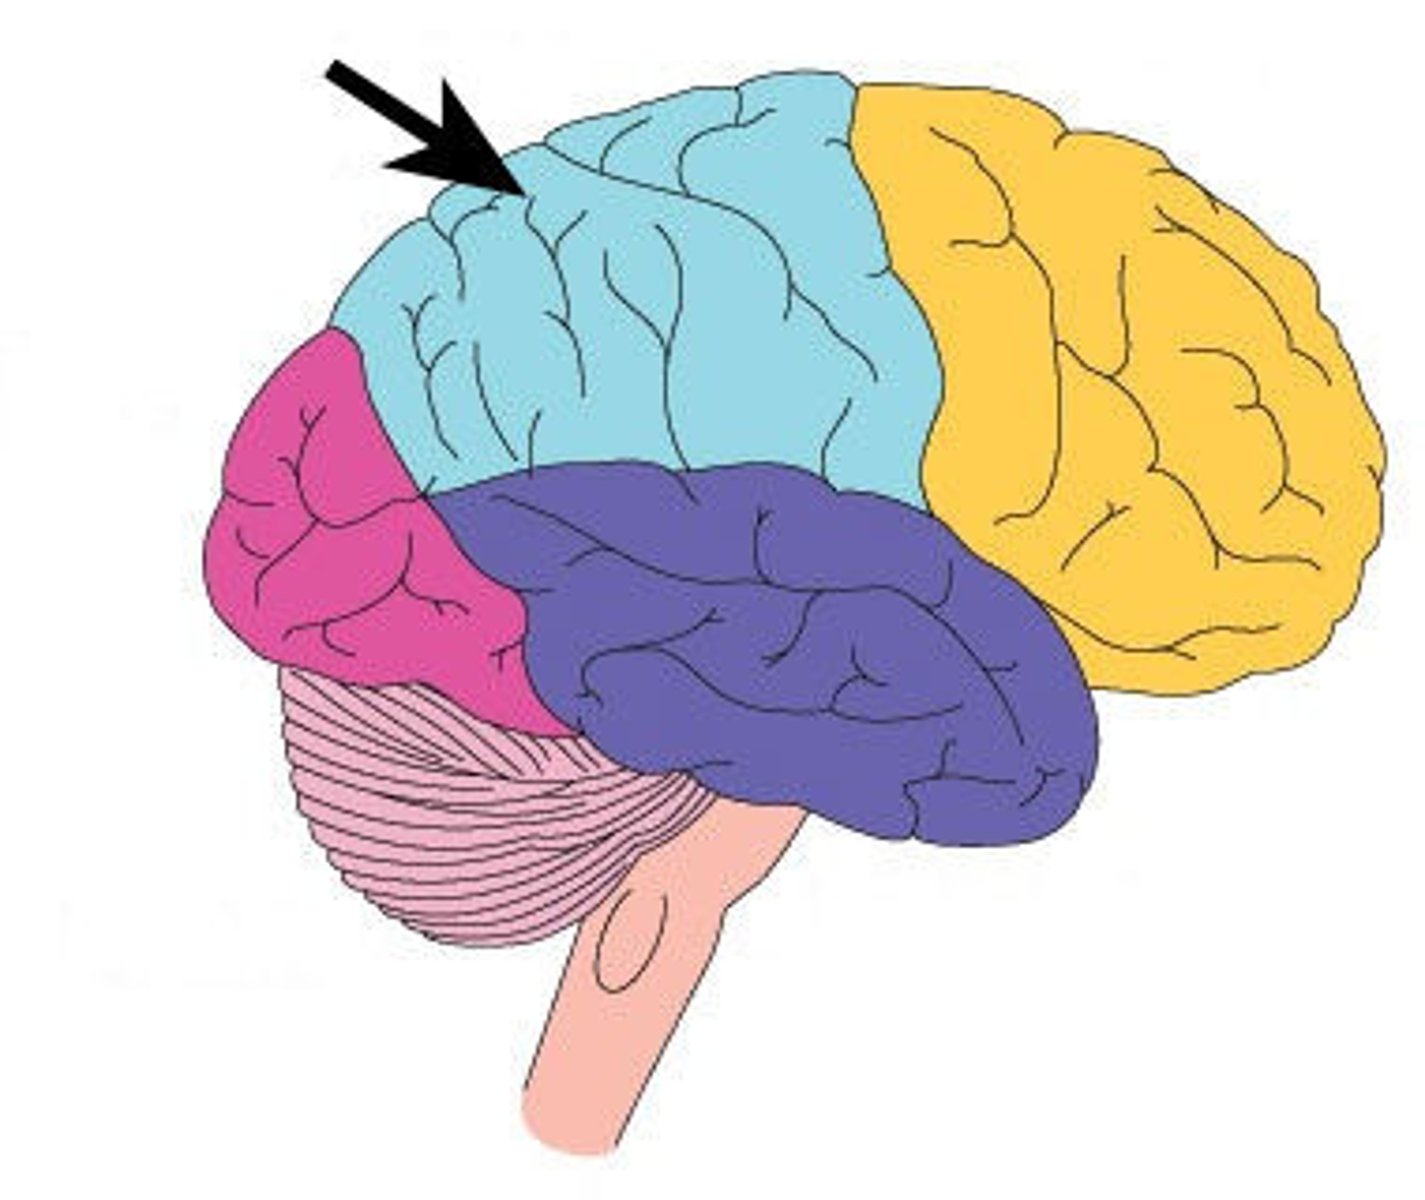

Parietal Lobe

What is this lobe?